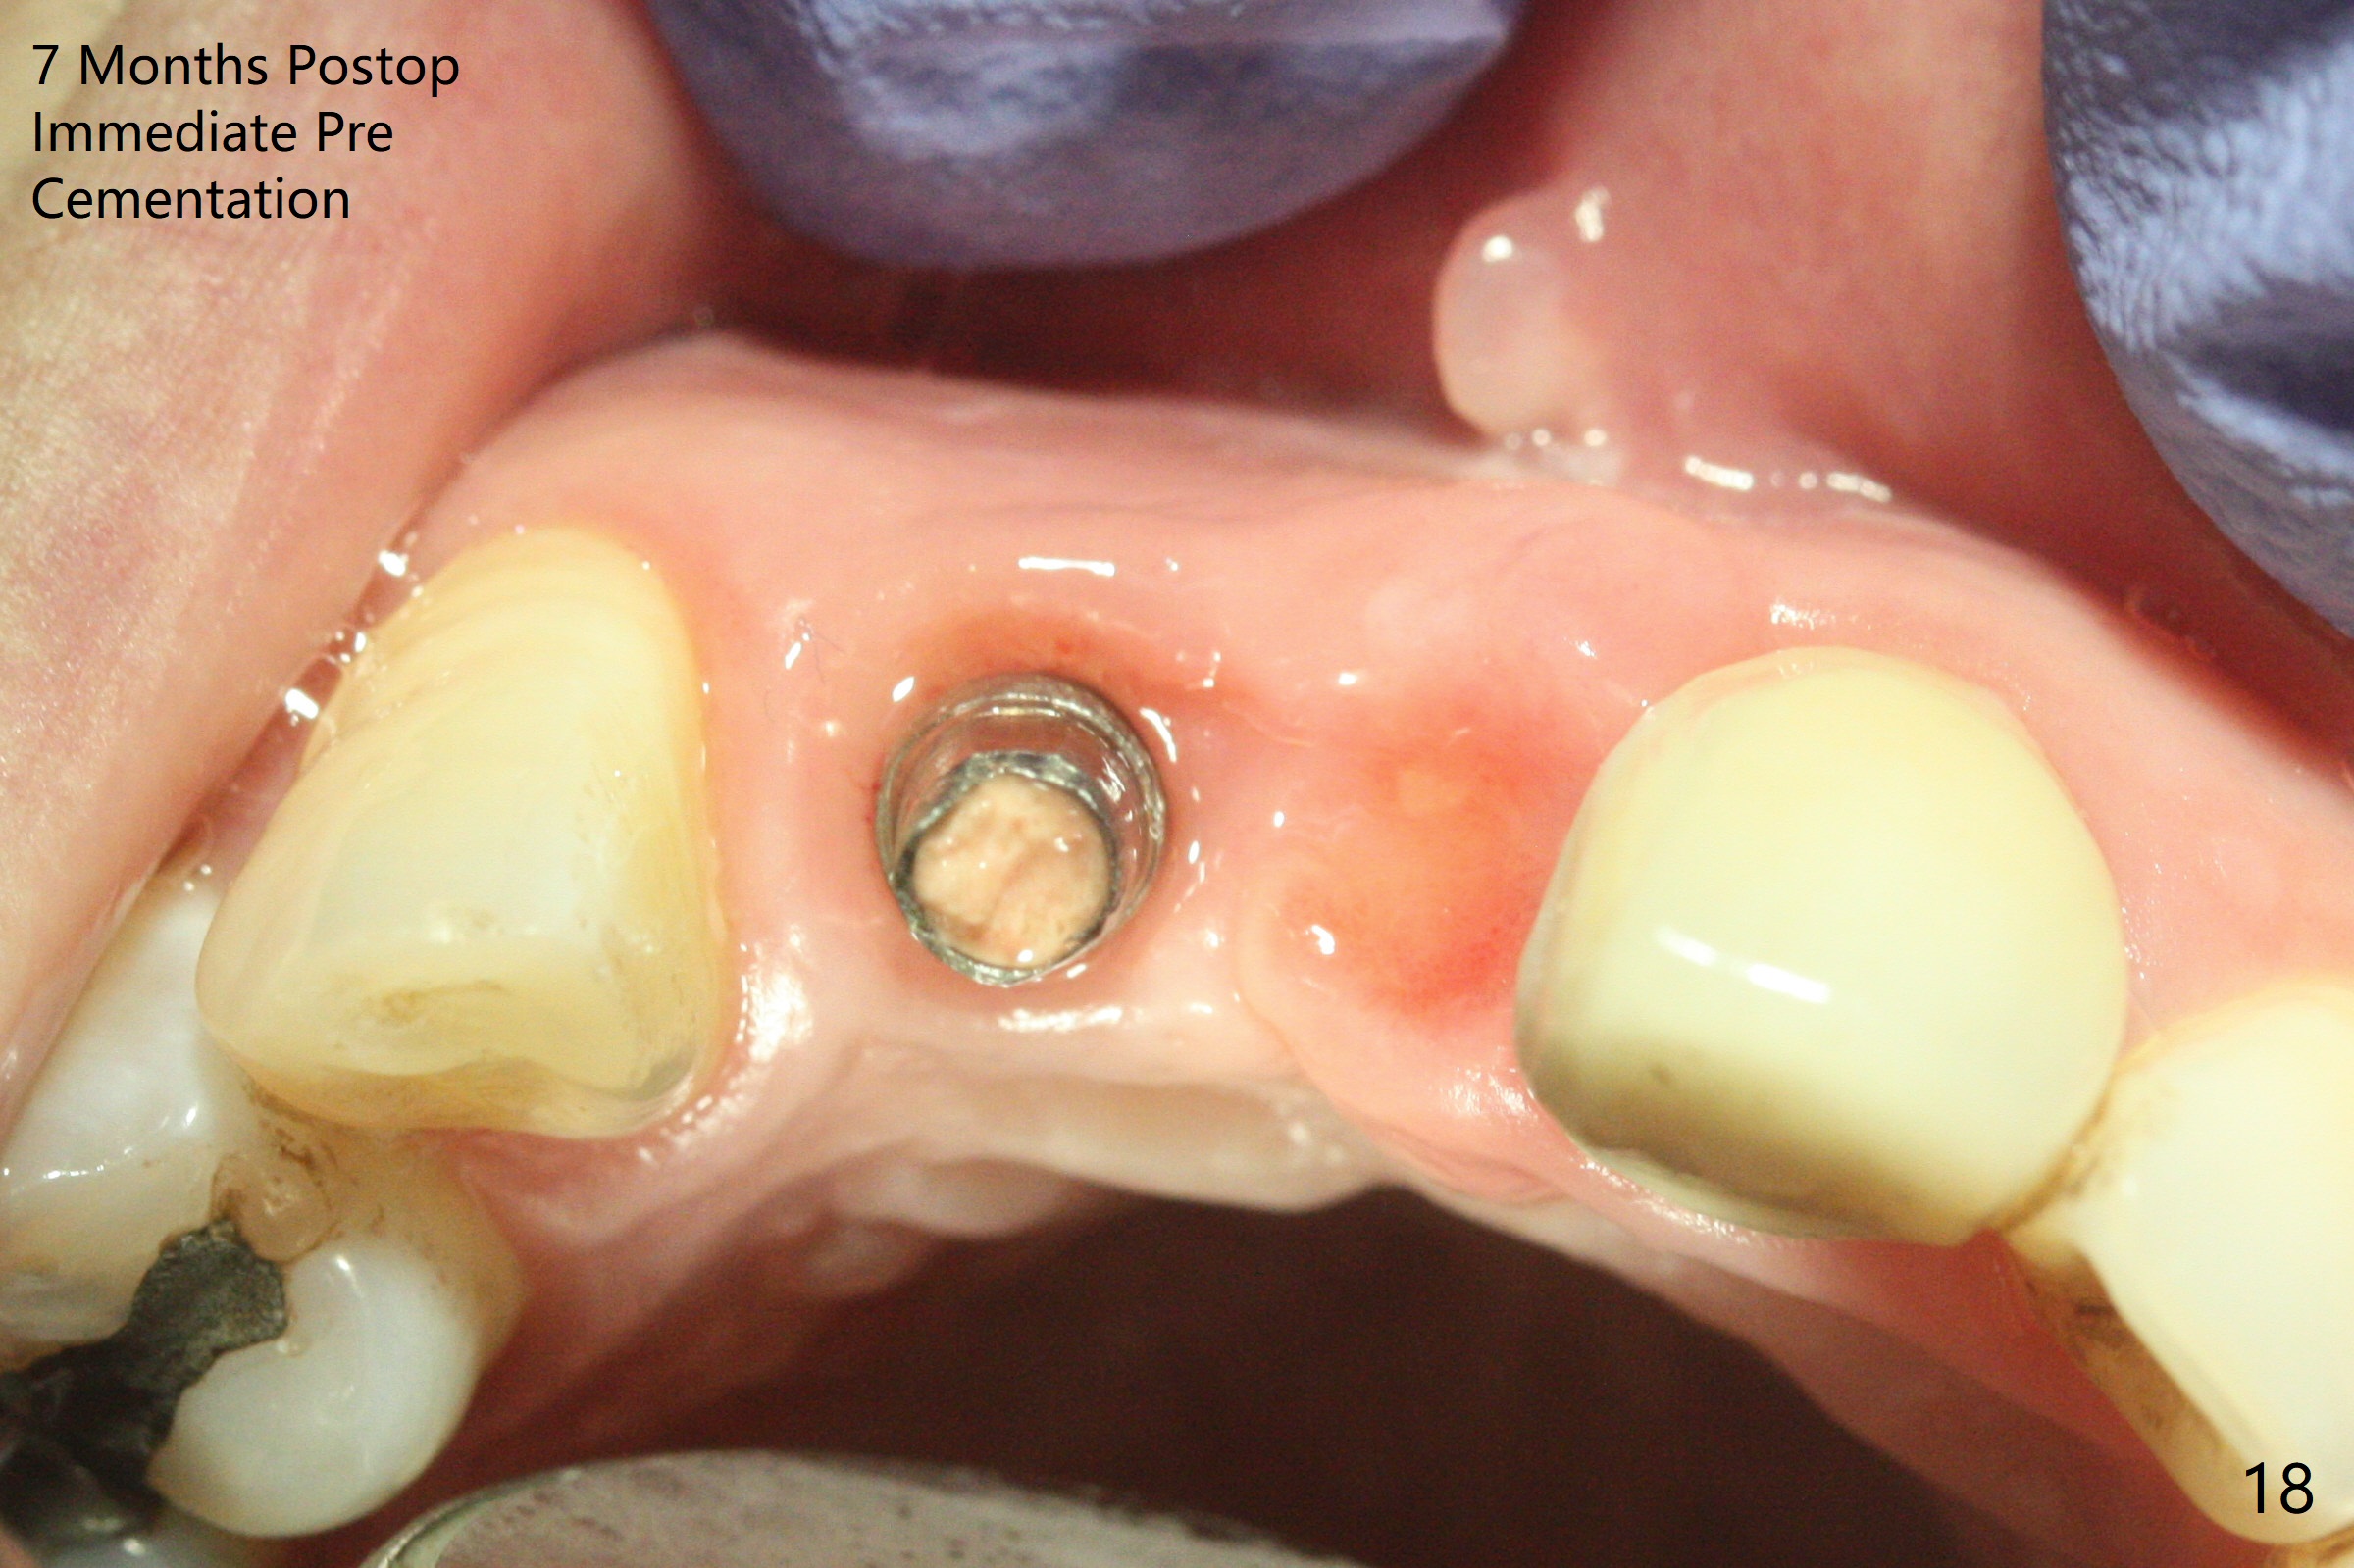

拆除部分桥发现:中,侧切牙牙龈红肿(图一),不利于切口和伤口愈合。不过还是在中切牙区切开,牙龈相当厚,有利于今后牙龈形成凹陷和乳头。坏消息是近远中距离太短,不利于植牙以及今后局部卫生维护,所以决定只在侧切牙种植(图二,三),完成钻洞后,颊侧根尖穿孔植骨,然后植入植体,即刻放置修复基台(图四 (*:牙龈乳头)),暴露基台牙龈缘,制作临时悬臂桥 (图五),两个中切牙牙冠长度差不多,插入临时桥时颊侧牙龈乳头基本形成(图六:*),缝合前颊侧,腭侧牙龈瓣下放置粘性骨块(图七,八:* )和PRF膜(图七:^)。最后使用牙周敷料。但愿术后牙龈炎症消失,形成良好牙龈乳头和pontic concavity。 其实由于口腔卫生习惯,术后十七天颊侧牙龈仍红肿(图九),而腭侧正常。如果口腔卫生改善而红肿依然存在,让实验室制作临时桥。术后一个月颊侧牙龈红肿好些(图十),好像骨粉丢失少许,可能与水枪使用有关。右上1牙冠显得太短(*)。也太肥大,因为右上1切缘太颊侧,与左上1对比(图十一:*)。由于颊侧牙龈(图十二:B)术中推向颊侧,与腭侧(P)牙龈之间放置大量粘性骨粉,术后一个月骨粉(<)形成牙龈,形成凹陷。颊侧萎缩不再明显了。右上1牙冠颈部多加些树脂,牙齿就显得长的多(图十三:箭头)。与侧切牙之间颈部故意留下间隙(*),让牙龈入位(空箭头),形成龈乳头。当右上1临时牙冠切缘(图十四:*)移到腭侧,外形改观不少。下次改善侧切牙唇侧。术后两个月三个星期牙龈红肿好像减轻,牙龈没有进入切牙间隙,干脆用树脂关闭(图十五:> <)。下次减少侧切牙切缘(^),适当增加中切牙长度(上提牙龈)。术后3.5个月植体好像整合,基台完全就位(图十六)。术后3.5个月Pontic凹陷形成,但是1,2之间龈乳头始终无法形成(图十七)。以后类似病例应该多种植一个。此例草率取模,可能需要临时粘固,观察植体近中颊侧所谓瘘道,必要刮治。由于比色不佳,需要实验室颜色更改,病人强化卫生,术后七个月,永久性牙冠粘固前,局部牙龈健康(图十八)。